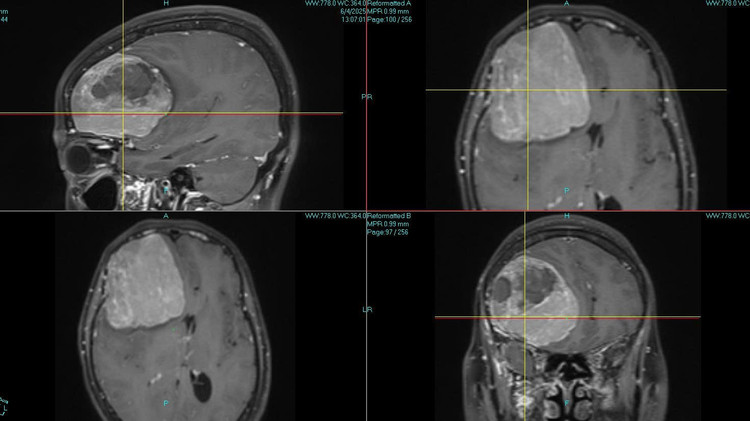

Tối ngày 3/6, các triệu chứng đau đầu, buồn nôn tăng lên nhanh chóng, đến sáng hôm sau bệnh nhân đã lơ mơ, không còn tỉnh táo. Ngay khi nhập viện, các bác sĩ tiến hành chụp cắt lớp vi tính sọ não, phát hiện người bệnh có khối u não kích thước lớn thùy trán phải đang chảy máu.

Hình ảnh khối u não kích thước lớn chảy máu vùng trán phải của bệnh nhân L. - Ảnh BVCC